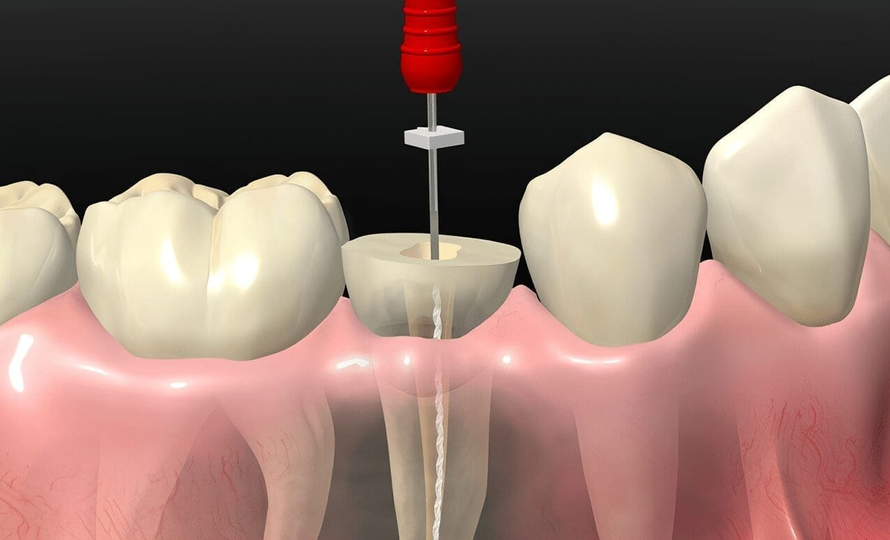

Tratamientos de conducto: conservación dental segura

El tratamiento de conducto, también conocido como endodoncia, es un procedimiento esencial para salvar dientes gravemente dañados por caries profundas o infecciones…